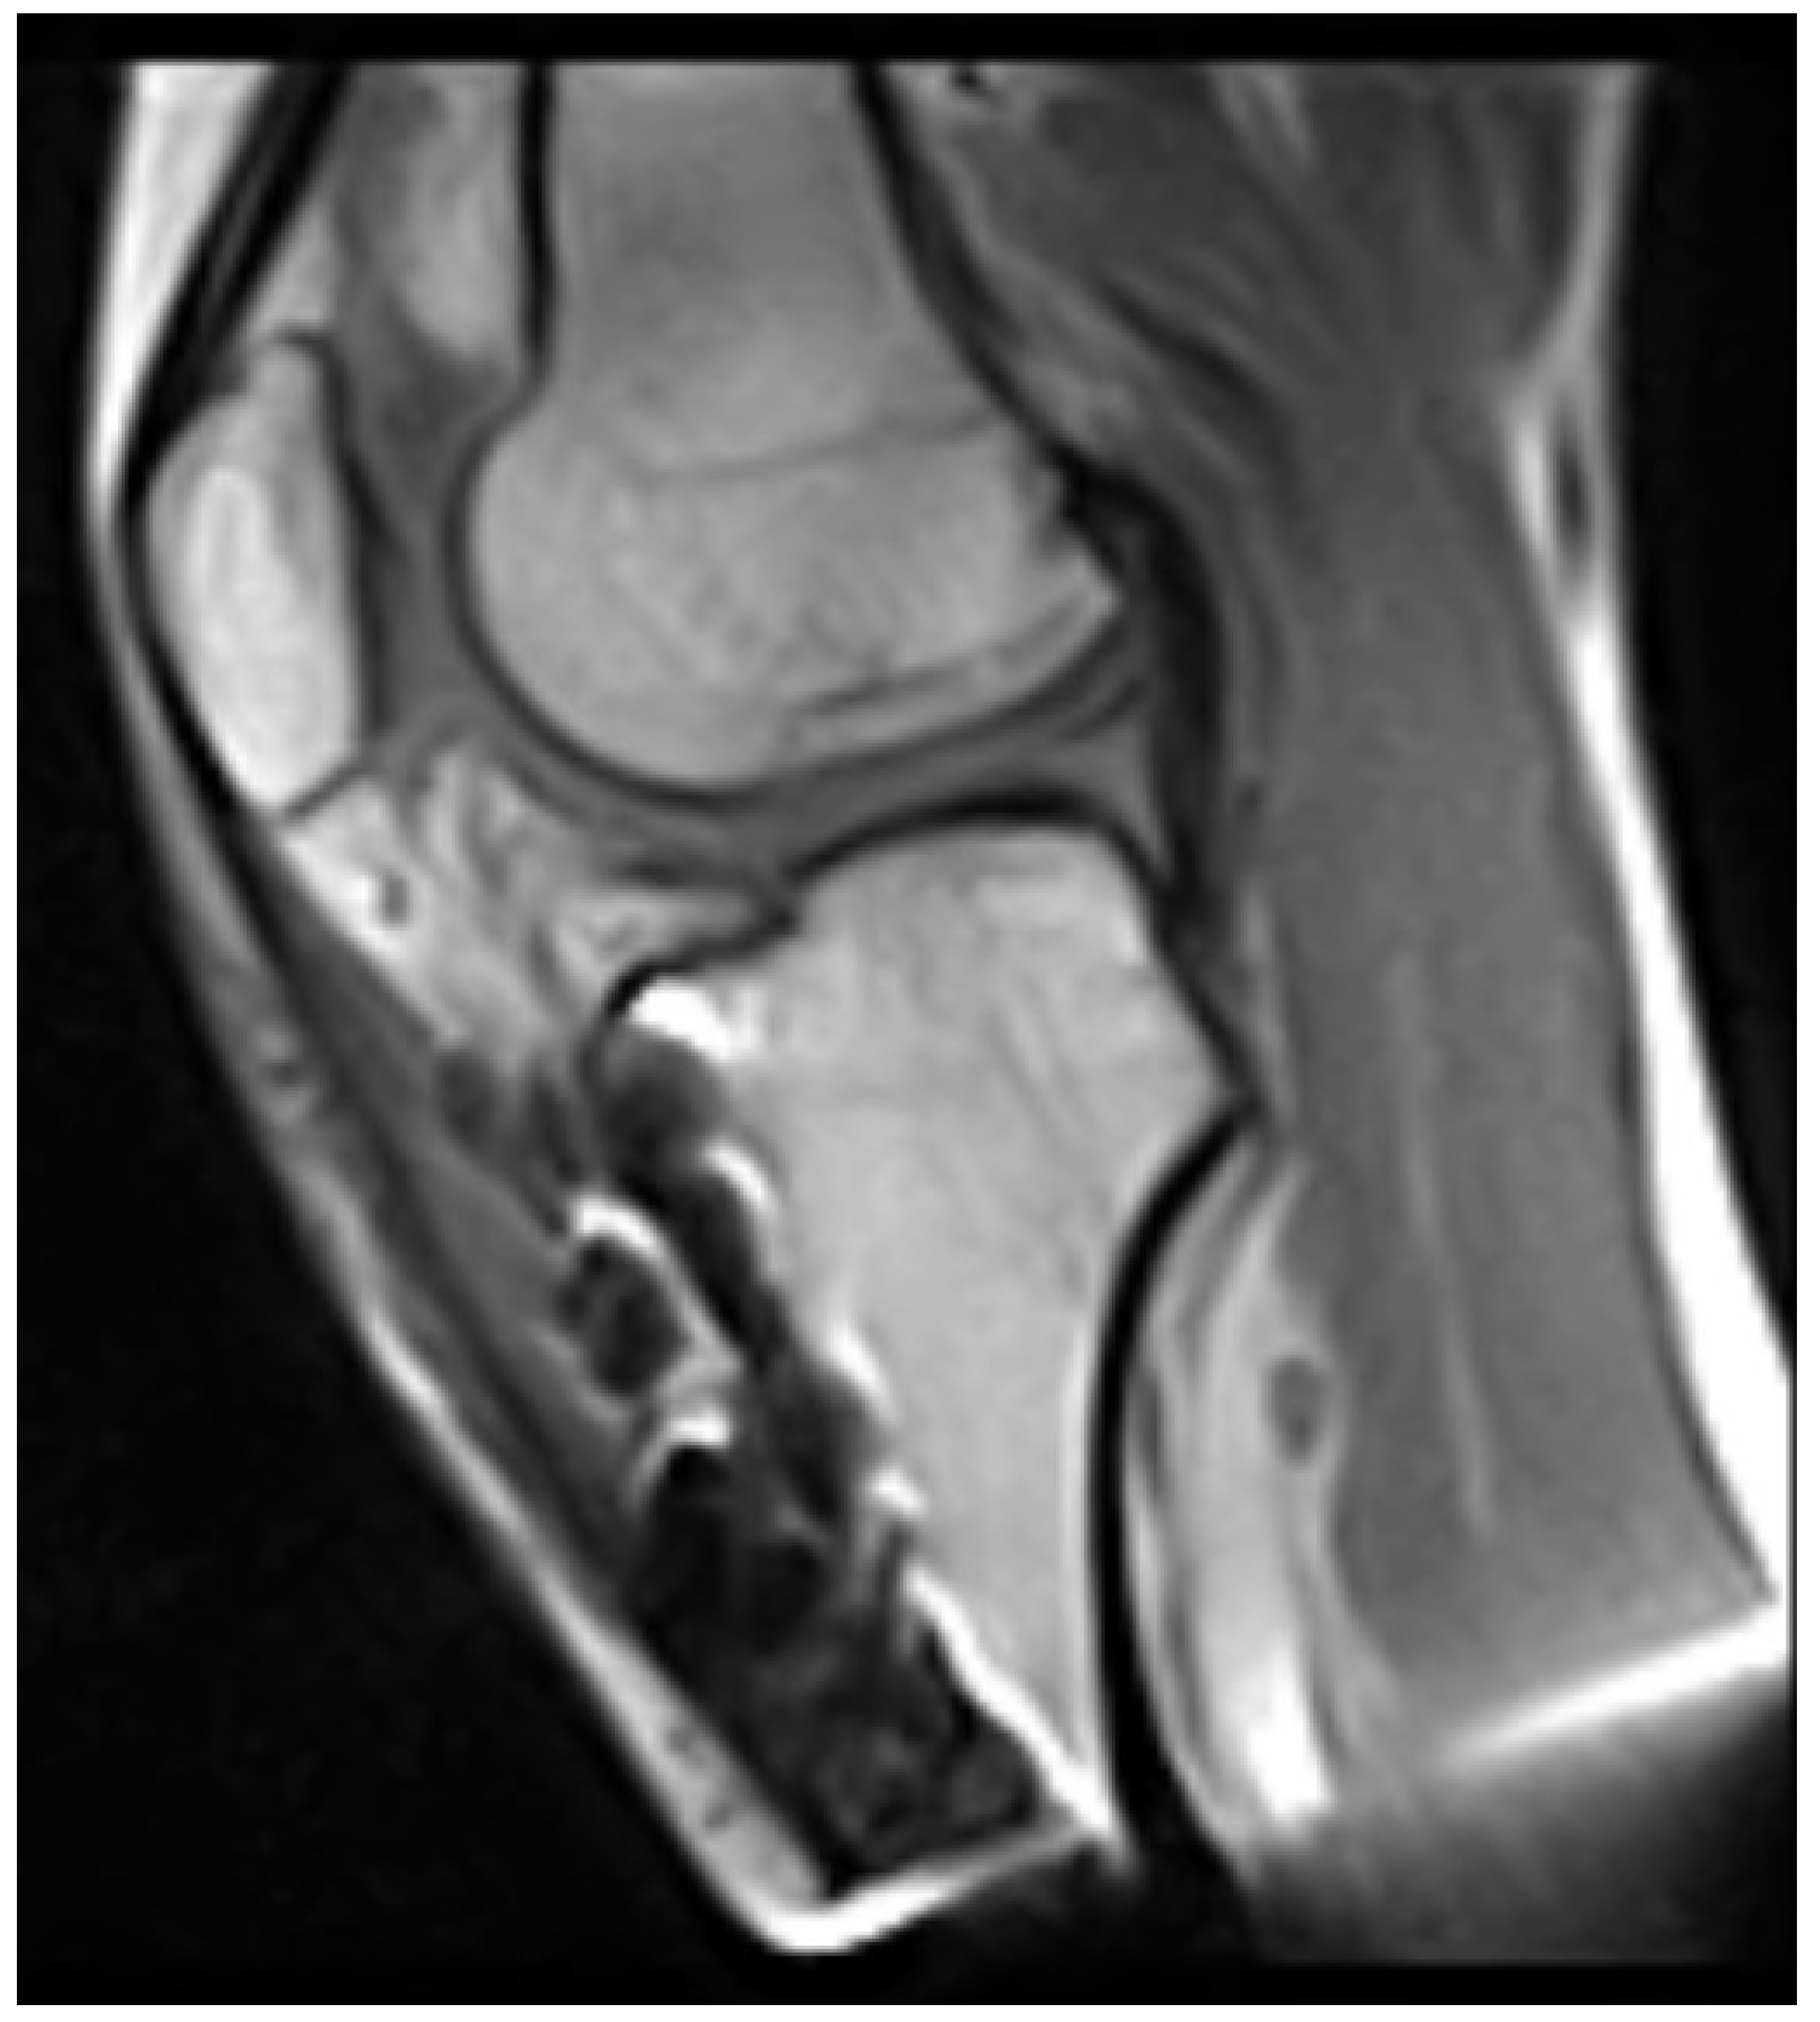

2 years later, at the age of 16, the tibial intramedullary nail was removed and finally, magnetic resonance imaging (MRI) of the knee was acquired. This showed complete agenesis of both the anterior and posterior cruciate ligaments (Figure 9) (Figure 10).

The patient underwent physical rehabilitation according to standard protocols and made a full recovery. Clinical follow-up showed complete knee range of motion and negative anterior and posterior drawer tests. Magnetic Resonance Imaging (MRI) at 6 months post-operation showed correct graft positioning and maturation (Figure 11) (Figure 12).